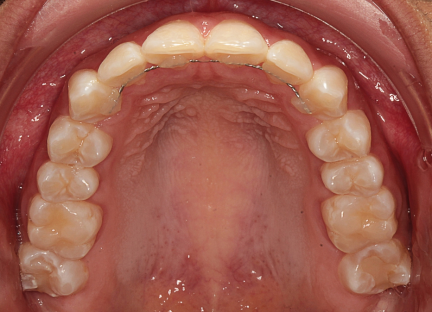

Classe II div 1, articulé croisé postérieur, surplomb accru, déviation de la ligne médiane maxillaire, rotations d'encombrement

Commentaires

- Elastiques de réduction interproximale et Classe II pour la correction de canine de classe II

- Dérotation et rétraction des incisives maxillaires

- Forme d'arcade ovale

- L'expansion molaire supérieure et les taquets multi-plans optimisés pour la rotation de la deuxième molaire inférieure ont été utilisés pour la résolution de l'occlusion croisée postérieure gauche

État initial

État final